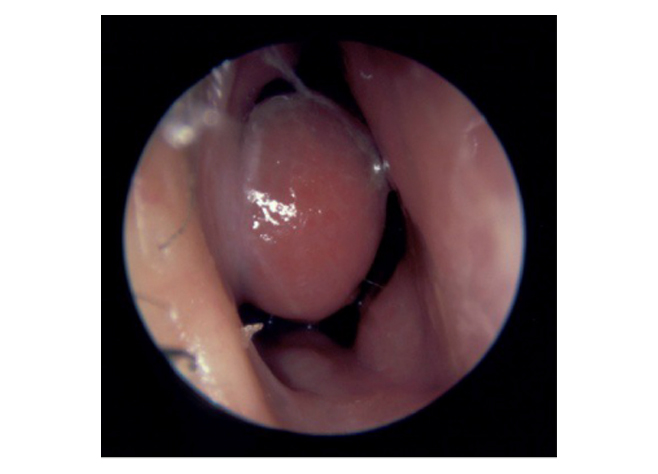

Ipertrofia del turbinato inferiore